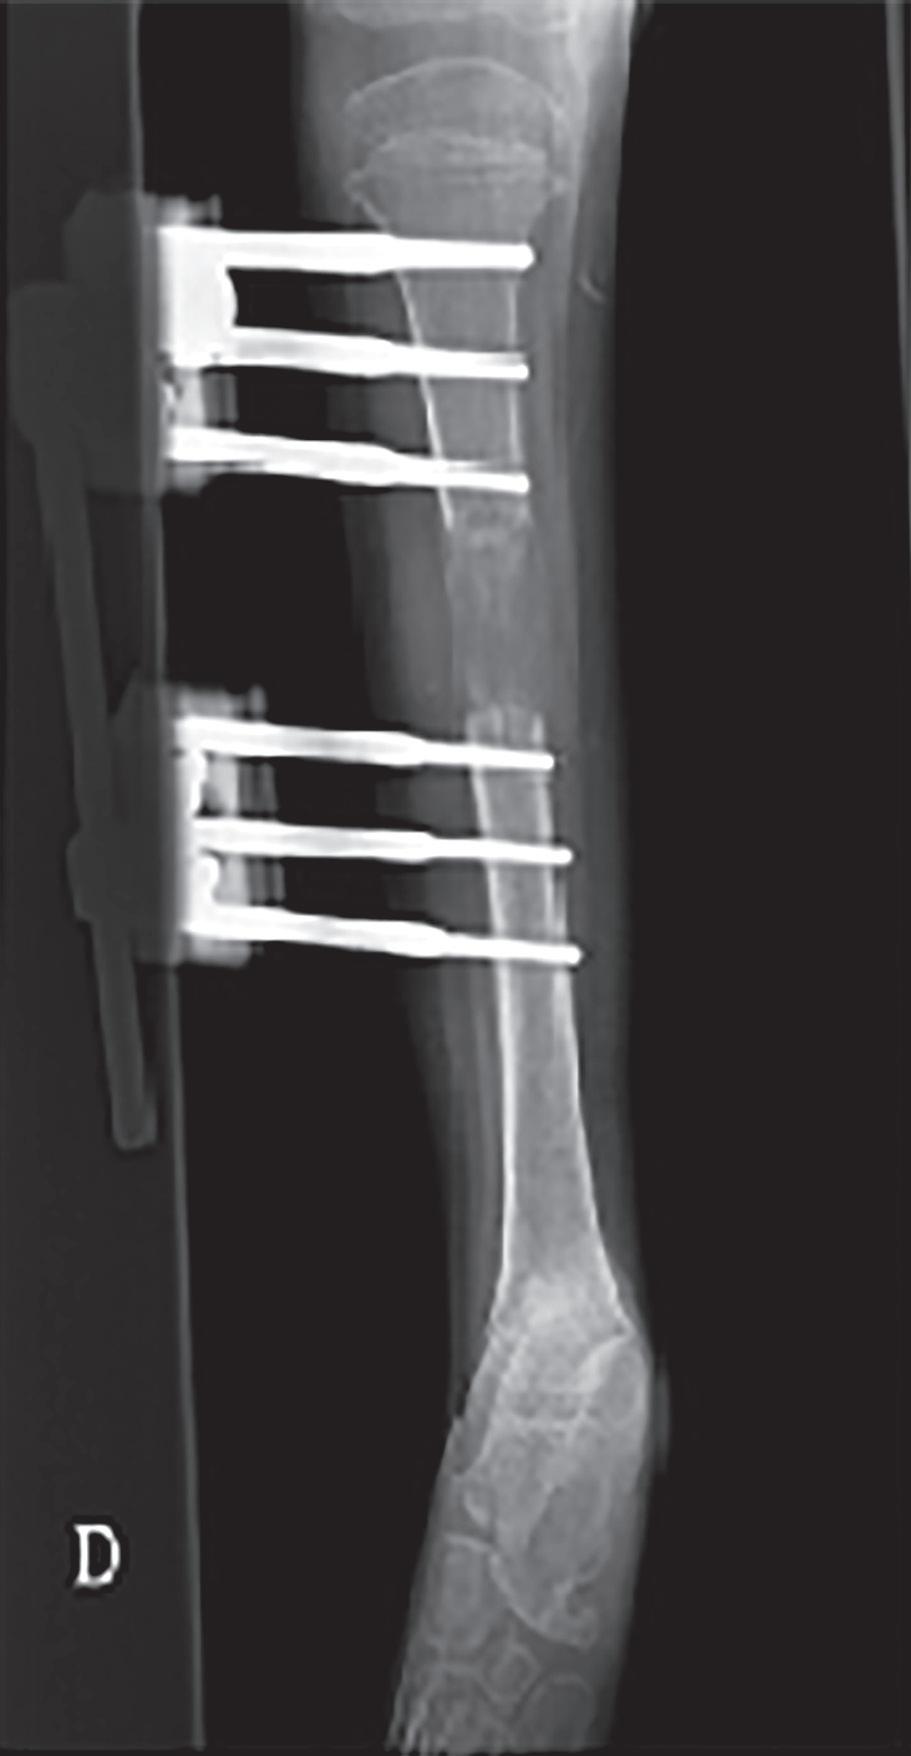

Mais recentemente, foi criada uma técnica para fazer o alongamento através de vareta endomedular aparafusada, que alonga através de ondas eletromagnéticas aplicadas externamente à pele do paciente (figura 44.5.4). Para correção de de formidades complexas existem sistemas de osteotaxia guiados por computador, geralmente com seis braços (hexapodais), como o Taylor Spatial Frame®, que permitem uma mobilização do fragmento a corrigir na direção que for necessária.

Figura 44.5.3 – Alongamento por osteotaxia, com fixador externo monoplanar.

Figura 44.5.4 – Alongamento por vareta eletromagnética aparafusada.

Em dismetrias abaixo dos 5-6 cm, o encurtamento ou travagem de crescimento poderão ser as melhores opções, dada a morbilidade e os riscos associados aos alongamentos; Existem múltiplos métodos de alongamento, que levam a uma osteogénese de distração. O alongamento por osteotaxia, historicamente, pode ser feito com os teotaxia por anéis (método de Ilizarov) ou através de distração por pinos em barra monoplanar (método de DeBastiani, figura 44.5.3).